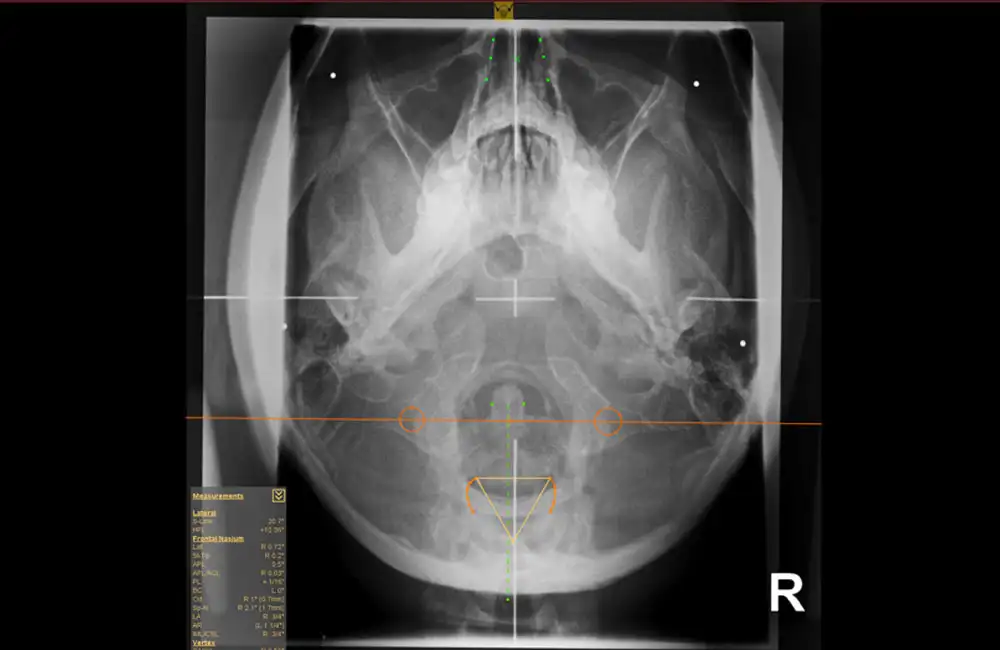

The dicomPACS® Upper Cervical (NUCCA) Chiropractic Tool Set was developed in close collaboration with leading NUCCA experts from the United States and Canada. It provides everything required for fast and highly precise diagnostics in the upper cervical spine. Specialized NUCCA templates such as the cephalometer, grid, circumscale, and relatoscope support a familiar workflow while ensuring maximum accuracy.

Using manual point marking, the software automatically generates midlines, reference points, curves, and angles, significantly improving the efficiency of diagnosis and treatment planning. The NUCCA Tool Set is complemented by all essential standard chiropractic tools, including distance and angle measurements, Cobb angles, and marker points—delivering a comprehensive, professional NUCCA analysis within a single, integrated solution.

Cephalometer, grid, circumscale, and relatoscope for precise analysis with a familiar workflow.

Automatic generation of midlines, reference points, curves, and angles based on manual point marking.

NUCCA-specific lines and structures such as the atlas plane line and S-line for accurate diagnostics.

All essential measurement and marking functions, including angle, distance, and Cobb measurements.